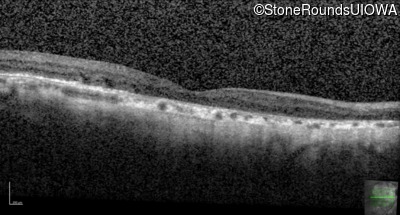

Optical Coherence Tomography - Right - 20/25 -2

Exemplar / OCT Stack